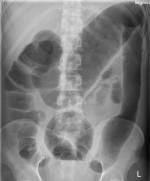

| B | • Bowel gas | • 3,6,9 rule - small bowel <3cm, large bowel <6cm, caecum and sigmoid <9cm |

| B | • Bones | • ribs, lumbar vertebrae, sacrum, coccyx, pelvis and proximal femurs |

| C | • Calcification • artifacts | • arterial Ca++, phelobliths, calculi • clips, tubes, implants |